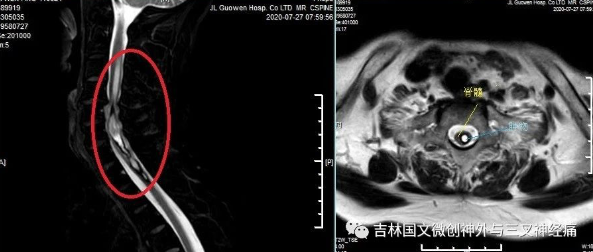

大娘姓李,62歲,家住梨樹縣。入院前約2年出現(xiàn)頸背部麻木感,當時未在意,約1年前進展為全身麻木感伴左側(cè)肢體運動欠靈敏。半年前于公主嶺**醫(yī)院檢查考慮為“脊髓內(nèi)占位”,家屬救治心切,輾轉(zhuǎn)四平及長春多家大醫(yī)院,因考慮到各種因素猶豫不決,一直到患者行走困難,需要輪椅代步進退兩難的境地時,才得知吉大一院的羅毅男教授在我院出診,于是抱著試試看的心態(tài)來到。

羅毅男教授及王芃主任接診病人,表示腫物位于髓內(nèi),且部位較高,手術(shù)風險極大,極易導致高危截癱。向家屬詳細介紹病情,并以有限的資金完善術(shù)前相關(guān)檢查,明確無手術(shù)禁忌癥后,行手術(shù)治療。手術(shù)由羅毅男教授及王芃主任團隊完成,歷時4時50分,手術(shù)順利完成,術(shù)后患者無明顯不適癥狀,四肢能動,活動自如。